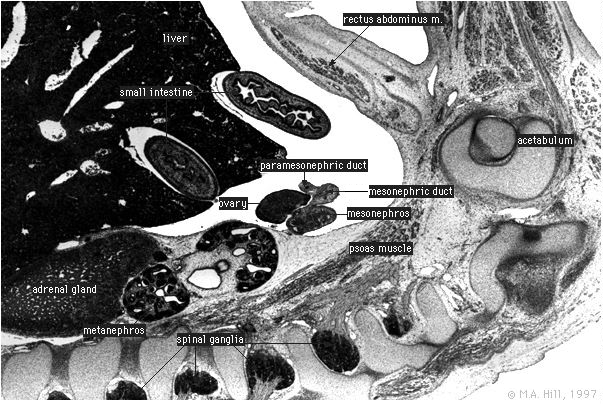

Human Embryo

Labelled Sagittal Section

High power only Labelled

Labels for paramesonephric and mesonephric ducts have been transposed on disc.